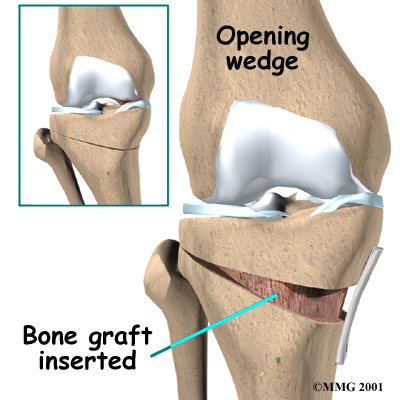

There are two methods to realign the knee joint. One involves taking out a wedge of bone; the other involves adding a wedge of bone. Any operation for cutting through a bone is called an osteotomy. In a closing wedge osteotomy, the surgeon cuts though the tibia on the lateral side, removes a wedge of bone, and pins the open edges together. In an opening wedge osteotomy, the surgeon cuts though the tibia on the medial side and opens a wedge, adding a bit of bone graft to hold the wedge open.

There are two methods to realign the knee joint. One involves taking out a wedge of bone; the other involves adding a wedge of bone. Any operation for cutting through a bone is called an osteotomy. In a closing wedge osteotomy, the surgeon cuts though the tibia on the lateral side, removes a wedge of bone, and pins the open edges together. In an opening wedge osteotomy, the surgeon cuts though the tibia on the medial side and opens a wedge, adding a bit of bone graft to hold the wedge open.

Opening Wedge Osteotomy

In the , an incision is made in the medial side of the knee. Again, care is taken to protect the nerves and blood vessels that travel across the knee joint.

Once the tibia bone is exposed, one cut is made through the upper tibia. A fluoroscope or X-rays are used to make sure the cut is in the right place.

After the bone is cut, the two sides of the tibia are separated to form a wedge-shaped opening.

This opening is then filled with bone graft. The bone graft is usually taken from pelvis bone, through an incision in the side of your hip.

The bone graft is held in position with a metal plate or pins.

After fixing the two edges of bone with a plate or pins, the surgeon stitches the skin together, and the leg is placed in a padded splint to protect the knee joint.

There are two methods to realign the knee joint. One involves taking out a wedge of bone; the other involves adding a wedge of bone. Any operation for cutting through a bone is called an osteotomy. In a closing wedge osteotomy, the surgeon cuts though the tibia on the lateral side, removes a wedge of bone, and pins the open edges together. In an opening wedge osteotomy, the surgeon cuts though the tibia on the medial side and opens a wedge, adding a bit of bone graft to hold the wedge open.

There are two methods to realign the knee joint. One involves taking out a wedge of bone; the other involves adding a wedge of bone. Any operation for cutting through a bone is called an osteotomy. In a closing wedge osteotomy, the surgeon cuts though the tibia on the lateral side, removes a wedge of bone, and pins the open edges together. In an opening wedge osteotomy, the surgeon cuts though the tibia on the medial side and opens a wedge, adding a bit of bone graft to hold the wedge open.